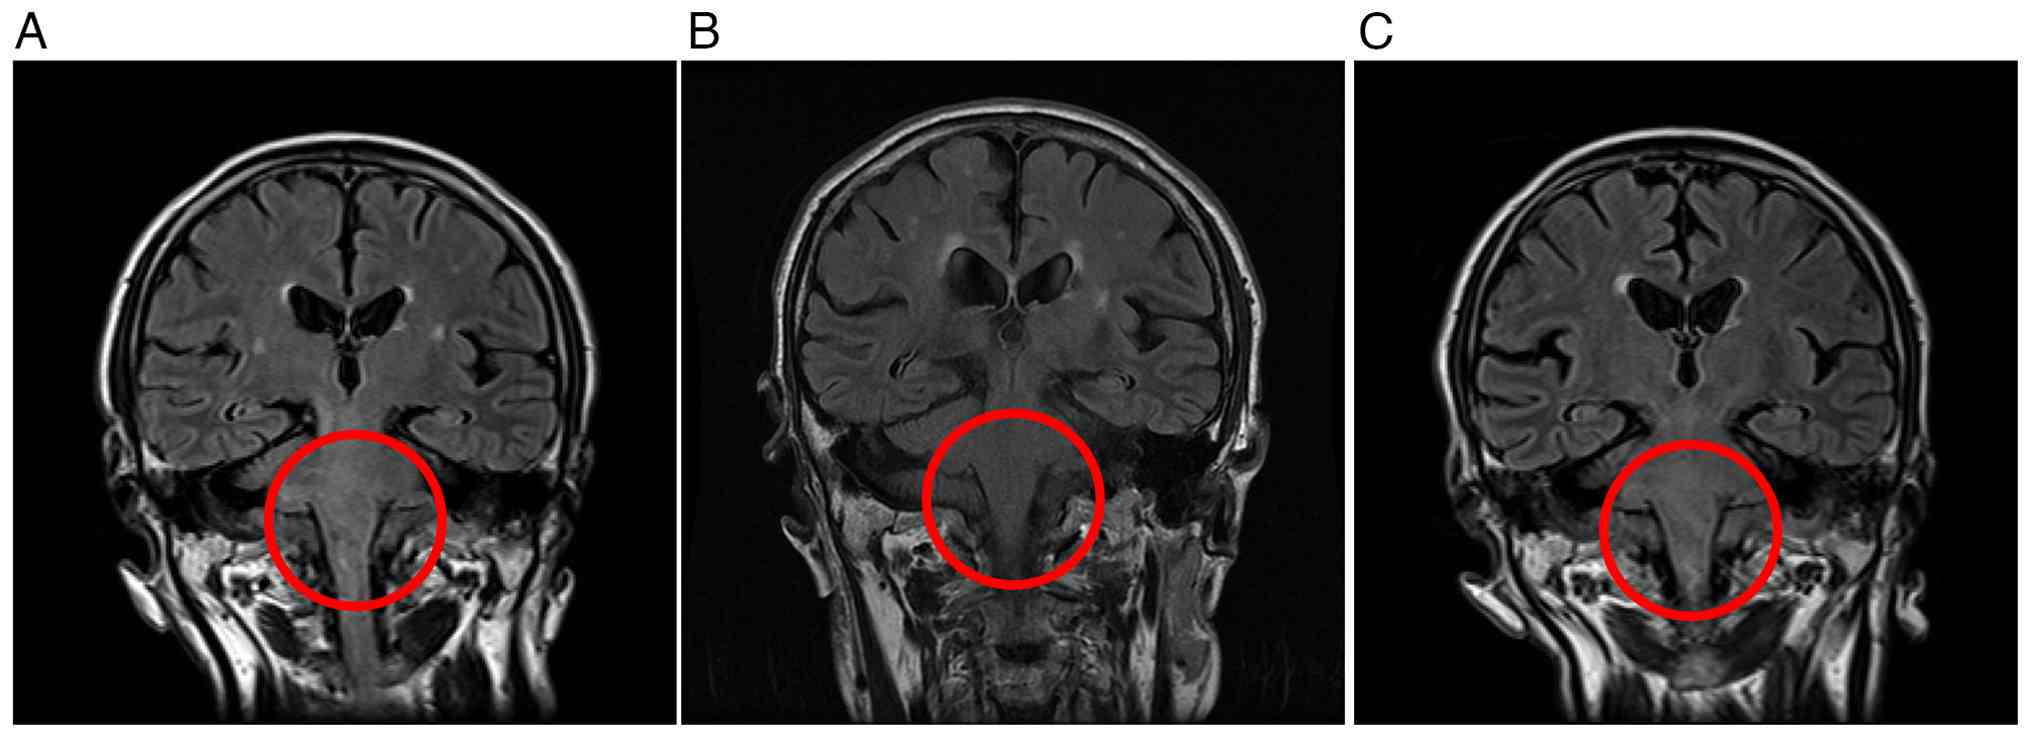

A 68-year-old man first presented in February 2023 to Tokyo Metropolitan Bokutoh Hospital (Tokyo, Japan) with weakness in the right leg and diplopia in the right eye. The diagnosis of primary central nervous system lymphoma (PCNSL) was established based on cerebrospinal fluid (CSF) cytology, immunocytochemical analysis and flow cytometric immunophenotyping, in conjunction with characteristic radiological findings. CSF cytology revealed clusters of atypical large lymphoid cells with irregular nuclei and prominent nucleoli. Immunocytochemical staining demonstrated strong membranous CD20 expression in the majority of atypical cells, and Ki-67 staining showed a high proliferative index. Flow cytometry confirmed a dominant B-cell population expressing CD19 and CD20. Given the typical MRI findings (Fig. 1A) and the clinical context, a diagnosis of PCNSL was made. A stereotactic brain biopsy was not performed due to the deep midbrain location of the lesion and the associated procedural risk. After diagnosis, the patient received intrathecal chemotherapy consisting of 40 mg/body prednisolone, 15 mg/body methotrexate and 40 mg/body cytarabine per administration. In parallel, the patient underwent methotrexate-based systemic chemotherapy combined with rituximab for four cycles. Rituximab was administered at 375 mg/m2 on day 1 of each 21-day cycle, and high-dose methotrexate was administered at 3,500 mg/m2 on day 3. Brain magnetic resonance imaging (Fig. 1B) demonstrated disappearance of the intracranial lesions, and the patient was judged to have achieved a complete response (CR). However, 3 months later, the patient relapsed and was treated again with four cycles of intrathecal MTX, cytarabine and steroids using the same dosing as previously applied. This was followed by whole-brain radiotherapy delivered at a total dose of 36 Gy in 20 fractions, which resulted in another CR. At 1-month post-CR, the patient presented with facial paralysis (inability to close the right eye), dysphagia and gait instability. Brain magnetic resonance imaging (MRI) confirmed a second relapse (Fig. 1C). Intrathecal MTX, cytarabine and steroids were reintroduced at the same dosage as previously applied, and tirabrutinib was initiated. Tirabrutinib was administered at a dose of 480 mg once daily on an empty stomach, which is the approved dose in Japan for the treatment of relapsed/refractory PCNSL. Owing to severe dysphagia caused by facial paralysis, a nasogastric tube was inserted and tirabrutinib was administered as a suspension through this once daily. Following a protocol similar to that reported by Yoshioka et al (9), six tablets of tirabrutinib (80 mg) were placed in a container, 20 ml of warm water at 55°C was added and the mixture was left for 10 min to dissolve. After confirming complete dissolution of the tirabrutinib tablets in the container, the resulting suspension was drawn into a syringe and administered via the nasogastric tube. To ensure complete administration of the suspension and prevent tube obstruction, the nasogastric tube was flushed with 20 ml of water after administering the suspension. Upon admission in November 2023, the patient received nutritional support via a nasogastric tube, and the facial paralysis gradually improved. Notably, the patient's dysphagia showed marked clinical improvement within 10 days of tirabrutinib initiation, allowing the patient to transition to an oral suspension (480 mg once daily) by day 11. By day 22, the patient was able to swallow food and tirabrutinib tablets. The patient was discharged on day 23, and oral tablets (480 mg once daily) were continued thereafter. No adverse events were observed during the suspension administration period.

Serial brain coronal fluid-attenuated

inversion recovery images of the brain. (A) At initial

presentation, hyperintense lesions were observed in the brainstem

region. (B) After chemotherapy, complete radiographic resolution of

the lesions was confirmed. (C) At second relapse, recurrent

hyperintense lesions were detected in the same anatomical region.

The red circles indicate the area of interest.

Figure 1.

Serial brain coronal fluid-attenuated inversion recovery images of the brain. (A) At initial presentation, hyperintense lesions were observed in the brainstem region. (B) After chemotherapy, complete radiographic resolution of the lesions was confirmed. (C) At second relapse, recurrent hyperintense lesions were detected in the same anatomical region. The red circles indicate the area of interest.